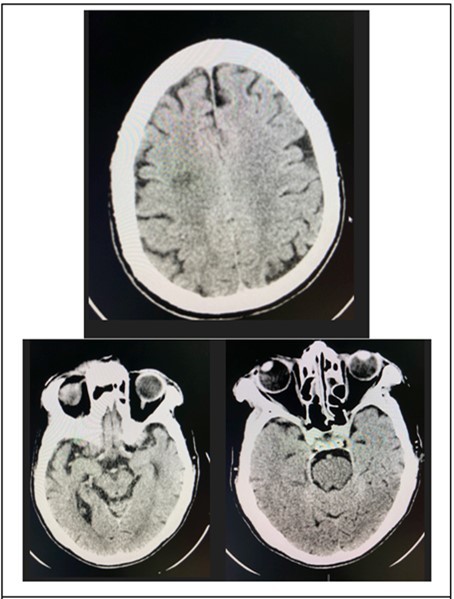

At the emergency room of the tertiary hospital, the patient had persistence of the diplopia and dizziness. The initial impression at that time was Cerebrovascular Infarct, thus a Plain Cranial CT Scan was done (conducted 6 hours after the onset of symptoms), which revealed a hypodense focus in the sub-cortical region of the right centrum semiovale extending to the right corona radiata, orbits, midbrain and pons were all normal. (Figure 2 and Figure 3)

Figure 4.Cranial CT Scan plain, axial of the patient done 6 hours after onset of diplopia, shows a hypodense focus in the sub cortical region of the right centrum semiovale extending to the right corona radiata

Figure 5.Cranial CT Scan plain, axial with orbital cuts of the patient which shows un remarkable orbit, midbrain and pons findings.